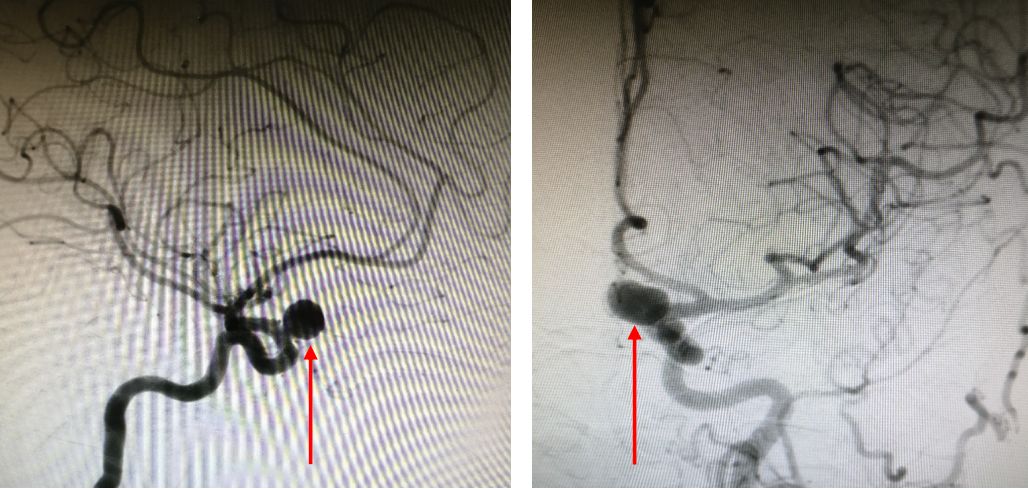

2. 术前DSA:

3. 术前3D-DSA: